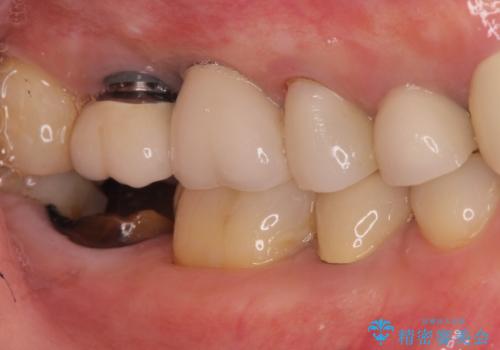

右下の奥歯を抜歯 インプラント治療による咬合回復

- 右下の奥歯をかぶせ物がとれたまま放置しているところに歯を入れたいとのことで来院されました。

精査すると保存が難しいため抜歯をして、インプラントを埋入、かぶせ物を装着する計画としました。

インプラント治療により、周りの歯を削ることなく咬合を回復することができました。